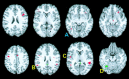

Functional magnetic resonance imaging (fMRI) was used to determine whether performance on lexical tasks was correlated with cerebral activation patterns. We found that such relationships did exist and that their anatomical distribution reflected the neurocognitive processing routes required by the task. Better performance on intramodal tasks (determining if visual words were spelled the same or if auditory words rhymed) was correlated with more activation in unimodal regions corresponding to the modality of sensory input, namely the fusiform gyrus (BA 37) for written words and the superior temporal gyrus (BA 22) for spoken words. Better performance in tasks requiring cross-modal conversions (determining if auditory words were spelled the same or if visual words rhymed), on the other hand, was correlated with more activation in posterior heteromodal regions, including the supramarginal gyrus (BA 40) and the angular gyrus (BA 39). Better performance in these cross-modal tasks was also correlated with greater activation in unimodal regions corresponding to the target modality of the conversion process (i.e., fusiform gyrus for auditory spelling and superior temporal gyrus for visual rhyming). In contrast, performance on the auditory spelling task was inversely correlated with activation in the superior temporal gyrus possibly reflecting a greater emphasis on the properties of the perceptual input rather than on the relevant transmodal conversions.